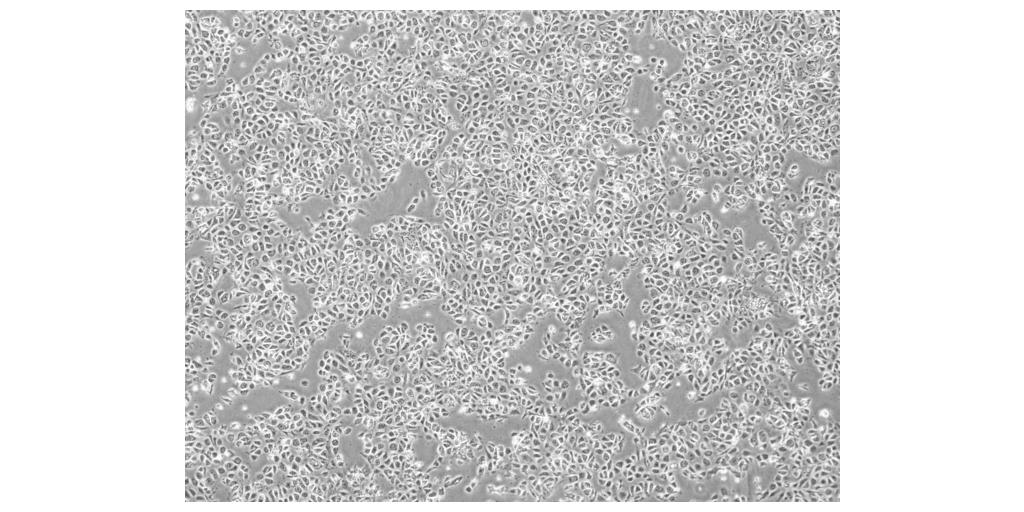

The collaboration is set to accelerate the development of Karis Bio’s innovative autologous iPSC-derived endothelial cell (iPSC-EC) therapy designed to generate new blood vessels in ischemic organs. Karis Bio’s first-in-human clinical study in South Korea leverages patient-specific iPSCs to restore blood flow and repair damaged tissues, offering patients a revolutionary alternative to conventional invasive procedures such as stents or bypass surgery, while eliminating the risk of immune rejection.

Cellino’s Nebula™ platform will enable scalable, high-quality production of autologous iPSCs, accelerating Karis Bio’s path to commercial scale. The Nebula™ platform is a closed-cassette, advanced biomanufacturing system that is both autonomous and deployable at the point of care, ensuring robust, reproducible, and contamination-free production. The initial phase of the collaboration focuses on industrializing autologous iPSC manufacturing, with plans to expand into Phase 2 trials through Karis Bio, USA (headquartered in Atlanta) in the U.S.